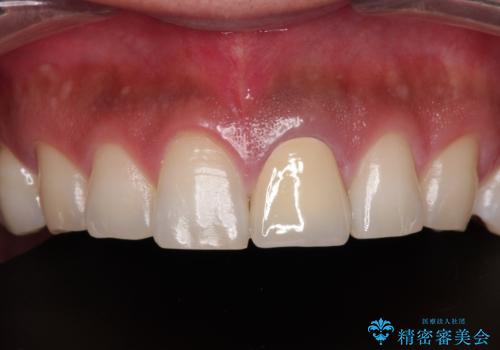

- 神経を取り除いたことで変色した前歯を気にして来院された患者様です。

根管治療はやり直さずに、ファイバーポストを使用した土台を植立してオールセラミッククラウンにて補綴することとしました。

神経を取り除いた歯は時間とともに変色してきます。

クリーニングやホワイトニングでは改善できないため、オールセラミッククラウンなどによる補綴治療が必要となります。